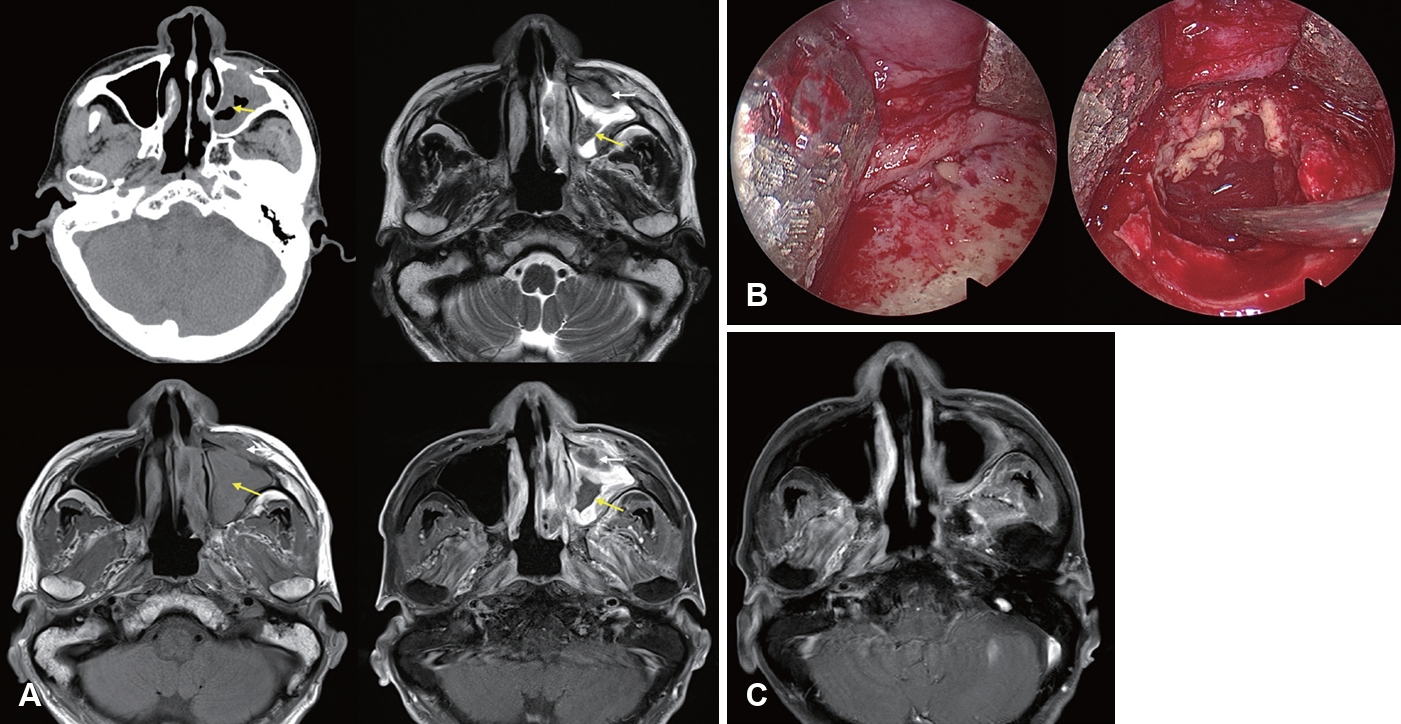

Nasal endoscopy is commonly used to evaluate suspected AIFRS patients by directly visualizing the nasal cavity. Key findings suggestive of AIFRS include mucosal edema, crusting, friability, tissue discoloration (pallor or darkening), ulceration, necrosis, and lack of sensation (Fig. 1). Although the procedure exhibits high specificity for detecting abnormalities, its sensitivity ranges considerably from 49% to 75% [19,23,38,41,42], indicating that negative findings cannot reliably rule out the disease.

Gadolinium-enhanced MRI (Gd-MRI) has emerged as a superior modality for evaluating IFRS. The “black turbinate sign” of sinonasal tissue lacking contrast enhancement on MRI was first described to correspond to devitalized mucosa from angioinvasive hyphae [54]. However, it should be noted that nonenhancing portions of the turbinate are observed in 30% of patients without IFRS, especially in the posterior portion of inferior turbinates. Non-enhancing turbinates in immunocompetent patients retain peripheral (likely normal) mucosa enhancement and thin septa, which are key features distinguishing pathologic black turbinates from infiltrative nonenhancing lesions (IFRS), which exhibit infiltrative non-enhancement extending to adjacent structures without a smooth, thin enhancing margin [55]. MRI had a higher sensitivity than CT for diagnosing AIFRS with similar specificity, PPV, NPV, and accuracy, and LoCE on MRI showed 76.5% agreement with endoscopic mucosal findings. Therefore, MRI is more sensitive than CT in detecting early changes of AIFRS and is an appropriate initial diagnostic method when AIFRS is suspected, given suspicious endoscopic findings [52]. In 2017, the American College of Radiology Appropriateness Criteria recommended that an MRI of the face and sinuses, including orbit and brain, is the study of choice for evaluating patients with suspected IFRS. CT may be a valuable complement to MRI for surgical planning [56].

Furthermore, Lagos, et al. [41] reported that LoCE (75% sensitivity, 84% specificity, 50% PPV, and 94% NPV), extrasinonasal extension (60% sensitivity, 89% specificity, 60% PPV, and 89% NPV), and orbit compromise (50% sensitivity, 95% specificity, 75% PPV, and 86% NPV) on MRI were significantly associated with AIFRS. Kim, et al. [13] highlighted the significance of the loss of contrast enhancement (LoCE) on MRI as a characteristic finding of AIFRS. LoCE reflects tissue ischemia secondary to angiocentric invasion by fungal organisms. MRI is particularly valuable for the early detection of AIFRS, evaluation of extrasinonasal extension, assessment of intracranial and intraorbital involvement, distinguishing between viable and necrotic tissues, guiding the extent of surgical debridement, and monitoring treatment response (Fig. 2) [13]. Furthermore, LoCE at the skull base was reported as an independent poor prognostic factor (hazard ratio [HR]= 35.846, p=0.004) in patients with extrasinonasal IFRS, possibly because extensive necrotic lesions at the skull base cannot be removed entirely. A rather extensive resection may lead to serious morbidity, such as internal carotid artery injury, untreated cerebrospinal fluid leakage, meningitis, or brain damage [14].

Our institution has established the principles for surgical management of IFRS based on evidence that postoperative extrasinonasal LoCE is significantly associated with mortality [13,14]. First, the extent of debridement is determined by intraoperative findings and preoperative imaging, particularly areas with LoCE on MRI. If necrotic tissue is identified during surgery and LoCE lesions found on preoperative Gd-MRI are in resectable locations without serious complications, the lesions are completely removed. CE lesions on preoperative Gd-MRI are not strictly removed and can be successfully treated with antifungal therapy, especially if located in the orbit or brain. Multiple debridement may be necessary based on disease progression. Endoscopic endonasal approaches are preferred when feasible. An open or combined approach may be required depending on the disease location, such as the anterior or inferior wall of the maxilla and hard palate. Orbital exenteration may be needed for extensive orbital involvement in patients with poor response to antifungal therapy. Urgent surgery is recommended upon diagnosis, especially for AIFRS. This strategy could reduce the IFRS mortality rate from 23.8% between 2003 and 2013 to 5.7% after 2013.